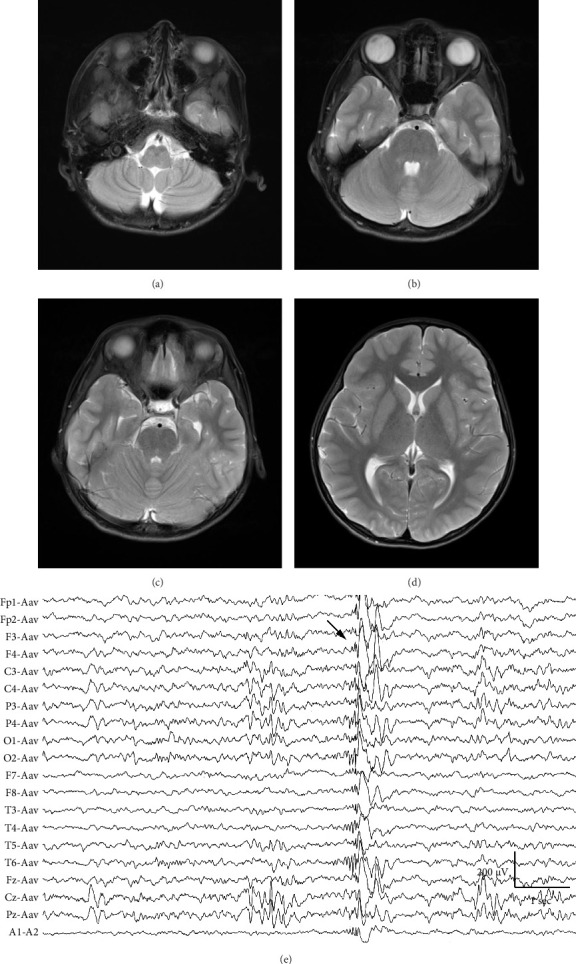

Background: Fibrodysplasia ossificans progressiva (FOP) is an ultra-rare disorder caused by heterozygous ACVR1 pathogenic variants and is characterized by both progressive heterotopic ossification of the soft tissues and congenital malformations of the great toe. In addition to pathological skeletal metamorphosis, patients with FOP experience diverse neurological symptoms such as chronic pain and involuntary movements; however, little is known about the association between FOP and epileptic seizures. Methods: We report the case of a young boy with FOP who sustained multiple major fractures due to epileptic loss of consciousness. Results: Based on generalized electroencephalographic abnormalities and the presence of myoclonic movements, the patient was diagnosed with juvenile myoclonic epilepsy. The absence of seizures was well-controlled with valproic acid, whereas occasional abrupt myoclonic movements of the hands and feet persisted. Conclusion: This case expands our understanding of the phenotypic diversity of FOP and the functional versatility of ACVR1-mediated bone morphogenetic protein (BMP) signaling.